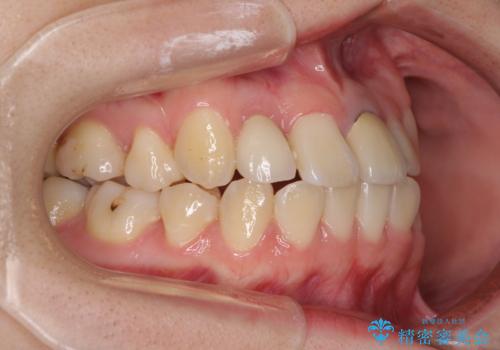

- 奥歯が痛いとのことで来院された患者様です。

上顎親知らず周辺の炎症と、神経組織の失活した歯の炎症による痛みが認められたため、親知らずの抜歯と根管治療を行いました。

根管治療を行った歯はクラウンによる補綴治療が必要となりますが、高校生の頃に行った矯正治療の後戻りも気になるとのことで、補綴治療を行う前に矯正治療を行うこととしました。

後戻りは軽度であり、インビザラインにて歯列を整え、その後にオールセラミッククラウンにて補綴治療を行うこととしました。